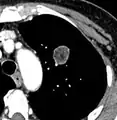

FDG-PET study of a 71-year-old woman with a solitary pulmonary nodule (thin arrow) in the left lower lobe near the heart. The scan also revealed abnormal increased activity at the gastro-esophageal junction (thick arrow). The final diagnosis was non-Hodgkin lymphoma at both sites.

If there is an intermediate risk of malignancy, further imaging with positron emission tomography (PET scan) is appropriate (if available). It can be done simultaneously as a CT scan in the form of PET-CT. Around 95% of patients with a malignant nodule will have an abnormal PET scan, while around 78% of patients with a benign nodule will look normal on PET (this is the test sensitivity and specificity).[15] Thus, an abnormal PET scan will reliably pick up cancer, but several other types of nodules (inflammatory or infectious, for example) will also show up on a PET scan. If the nodule has a diameter of less than one centimeter, PET scans are often avoided because of an increased risk of falsely normal results.[15][16][17] Cancerous lesions usually have a high metabolism on PET, as demonstrated by their high uptake of FDG (a radioactive sugar).